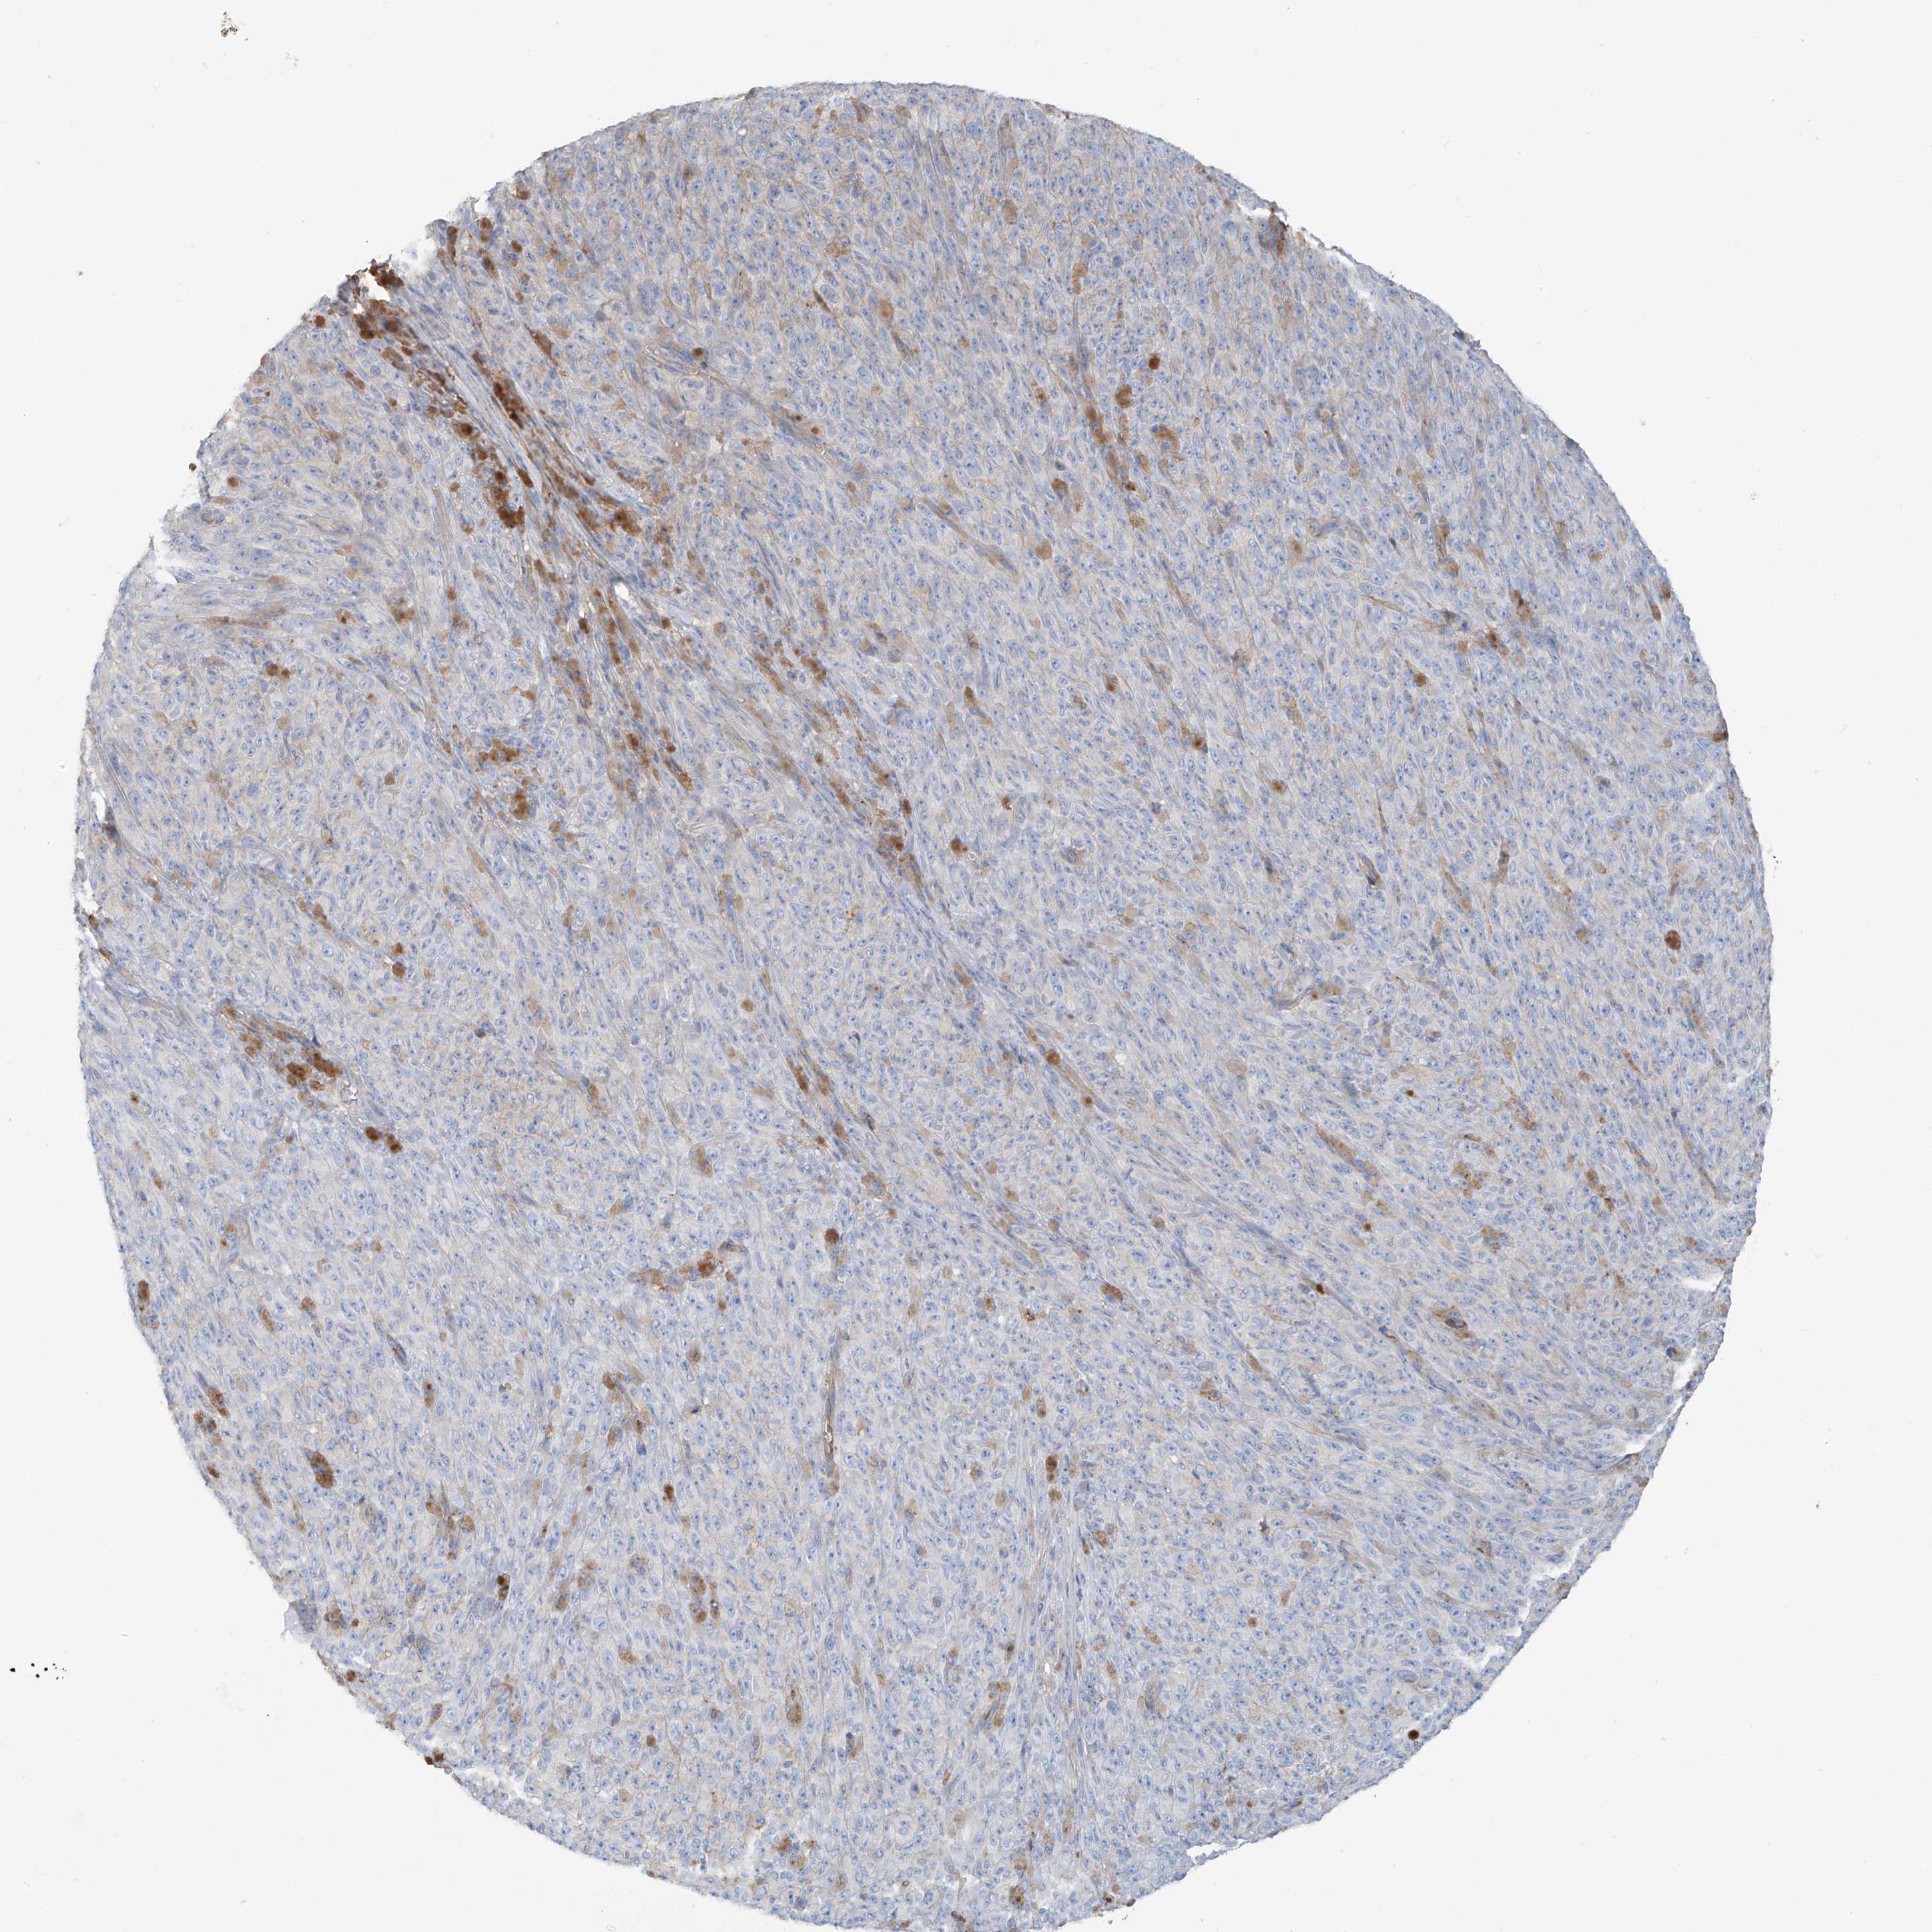

MELANOMA - Protein expressioni

A mouse-over function shows sample information and annotation data. Click on an image to view it in a full screen mode. Samples can be filtered based on level of antibody staining by selecting one or several of the following categories: high, medium, low and not detected. The assay and annotation is described here.

Note that samples used for immunohistochemistry by the Human Protein Atlas do not correspond to samples in the TCGA dataset.

Antibody stainingi

Antibody staining in the annotated cell types in the current human tissue is reported as not detected, low, medium, or high, based on conventional immunohistochemistry profiling in selected tissues. This score is based on the combination of the staining intensity and fraction of stained cells.

Each image is clickable and will lead to virtual microscopy that enables deeper exploration of all samples and also displays staining intensity scores, fraction scores and subcellular localization as well as patient and tissue information for each sample.

Antibody HPA009134

Staining

High

Medium

Low

Not detected

Intensity

Strong

Moderate

Weak

Negative

Quantity

>75%

75%-25%

<25%

None

Location

Nuclear

Cytoplasmic/membranous

Cytoplasmic/membranous,nuclear

Malignant melanoma, NOS

Malignant melanoma, Metastatic site